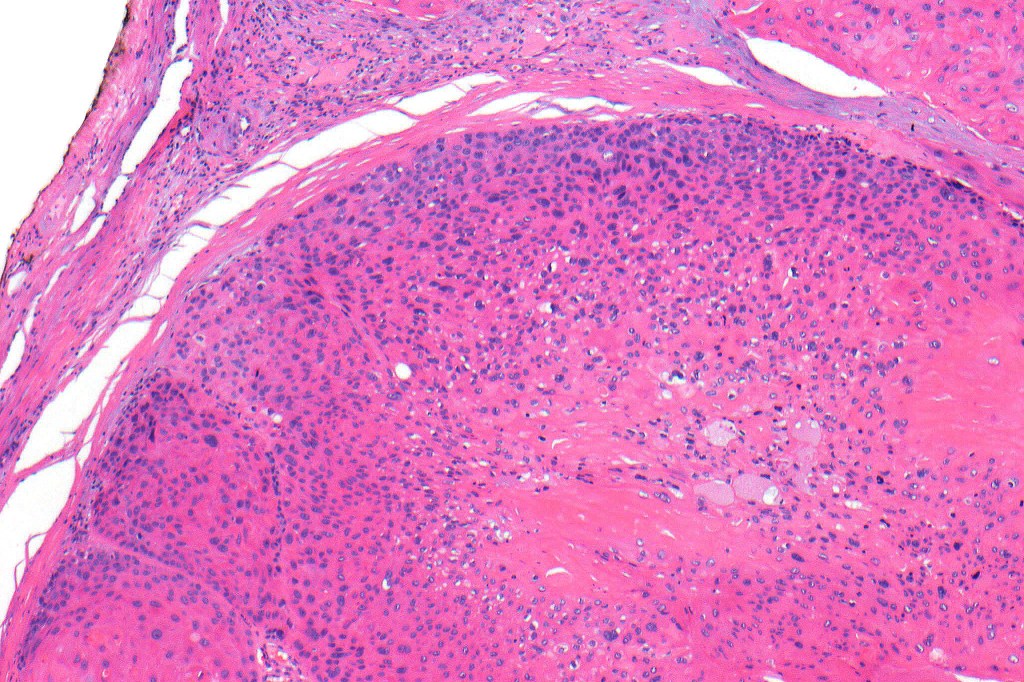

•Infiltrating tumor arising from the wall of a pilar cyst

•Malignant change within a proliferating pilar tumor

•Nuclear pleomorphism and nuclear hyperchromatism

•Marked mitotic activity